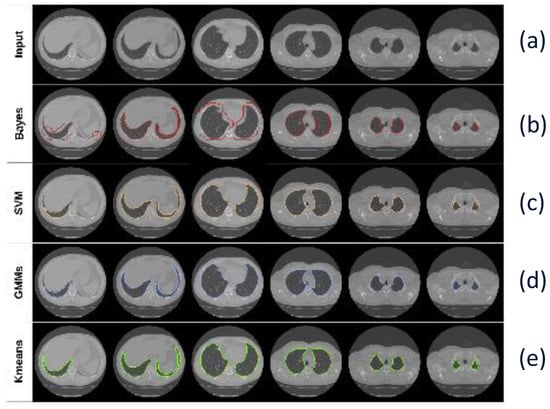

5. Lung Segmentation

- Hofmanninger, J.; Prayer, F.; Pan, J.; Röhrich, S.; Prosch, H.; Langs, G. Automatic lung segmentation in routine imaging is primarily a data diversity problem, not a methodology problem. Eur. Radiol. Exp. 2020, 4, 1–13. [Google Scholar] [CrossRef] [PubMed]